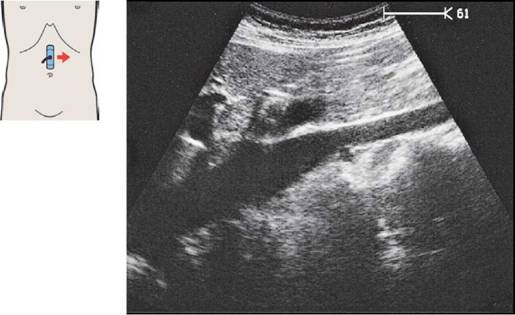

41 Почечная вена на уровне ворот почки, почечная артерия

29 Почечная артерия

Правая почечная артерия и вена при поперечном сканировании

Почечная артерия идет так же, как и почечная вена с небольшим каудальным отклонением то нее.

Почечная артерия расположена сзади и каудальнее почечных вен.